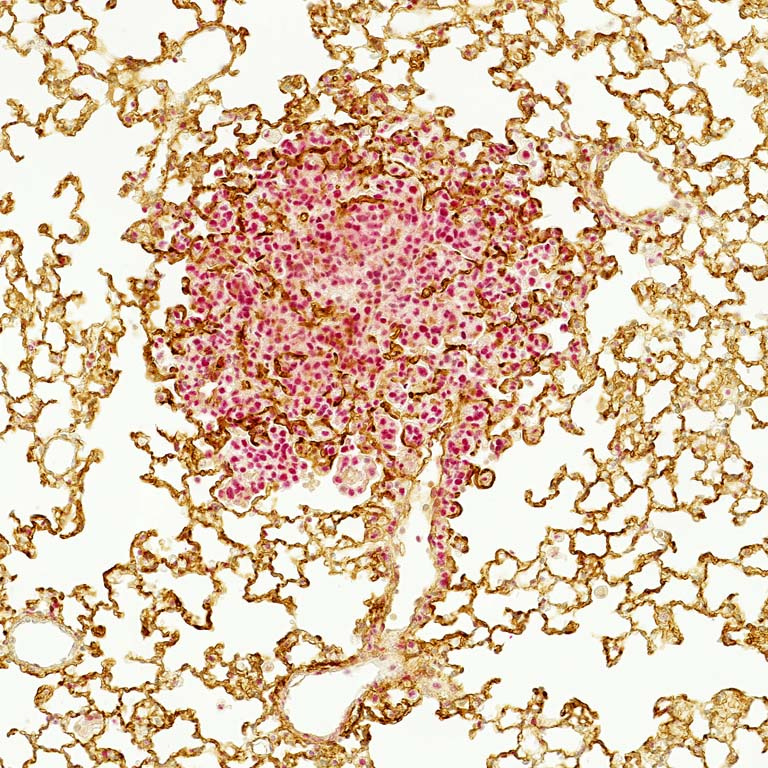

The presented image shows a section through a tumor-bearing lung lobe of a mouse that received immunogenic drugs. In the center of the image, a lung cancer tumor nodule is shown, with tumor cells highlighted by nuclear staining (red), surrounded and permeated by a vasculature meshwork (brown).